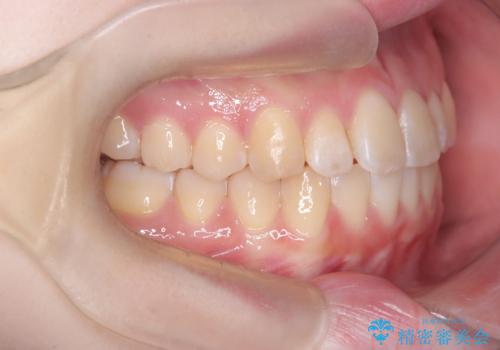

【インビザライン】オープンバイト。凸凹を治したい

- オープンバイトを主訴に来院されました。

インビザラインを用いIPRと遠心移動を行いオープンバイトと叢生の改善を行なっております。

前歯の叢生がわずかにありますが、追加アライナーの作成は希望されなかったため、歯を動かしていく動的治療は終了となりました。